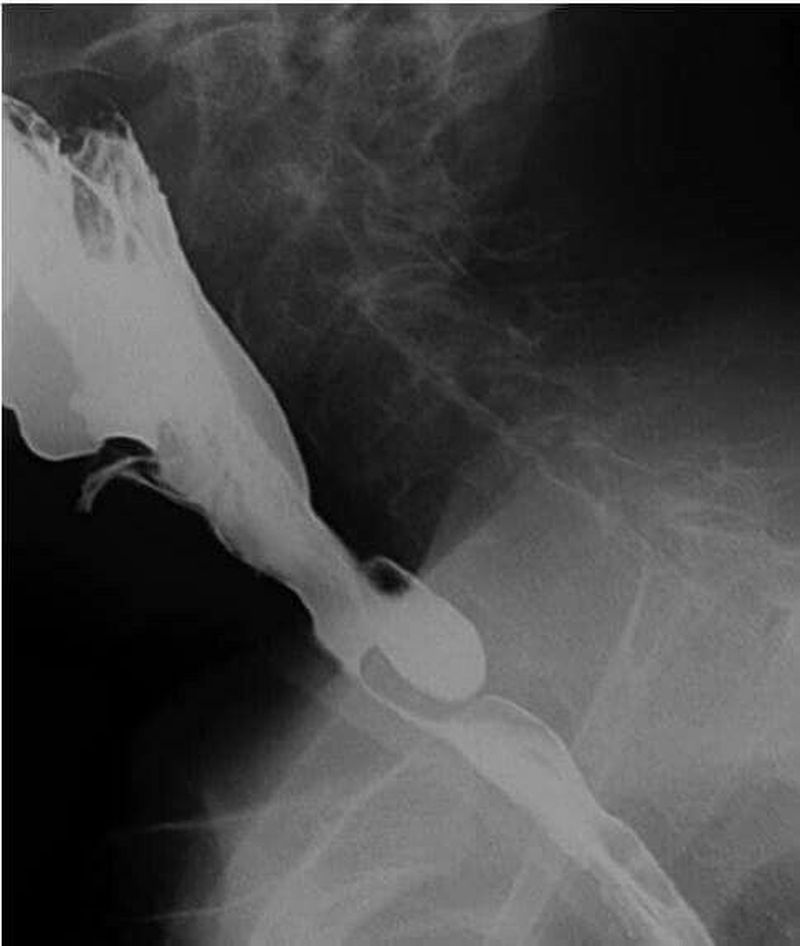

The above shown is a fluoroscopic image of hypopharyngeal pouch A midesophageal diverticulum is caused by inflammation located in the chest cavity outside the esophagus that pulls on theesophagus or is caused by esophagealmotility disorders. When a diverticulum increases in size, the following symptoms may appear: Dysphagia (difficulty swallowing) Regurgitation (return of undigested food back into the mouth) Sense of a lump in the neck. Halitosis (smelly breath) due to stagnant food in the pouch.đ¤đ¤đ¤ Cough, especially at night.Hoarseness (voice change) Sometimes pneumonia toođ¤